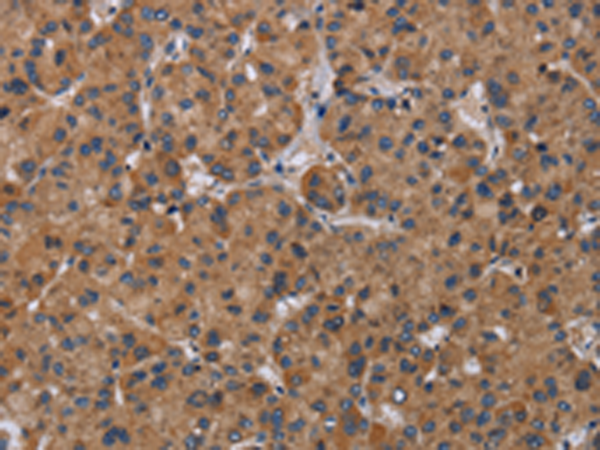

分类: 科研抗体货号: P08528别名: p8; C6.1B; MTCP1; MTCP1B; MTCP1NB; p8MTCP1应用: IHC反应种属: Human, Mouse